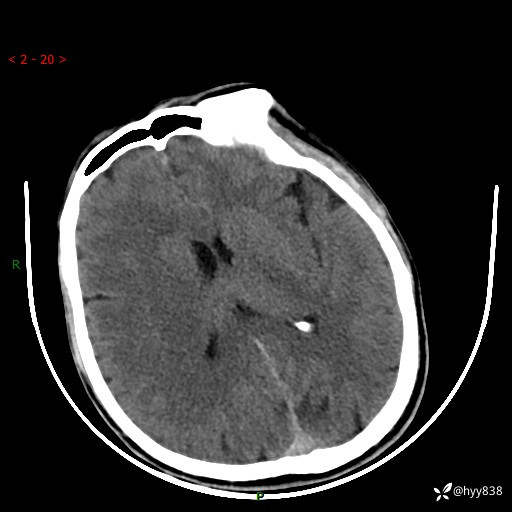

颅脑CT平扫